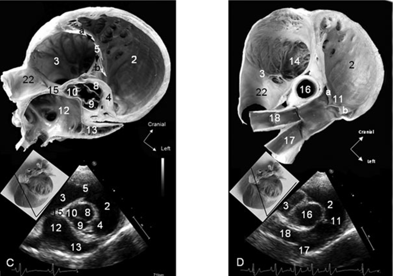

What view is this and at what level?

Right parasternal short axis view

LV @ pap mm level

Right parasternal short axis @ chorda tendinae

What view and level is this?

Right parasternal short axis @ mitral valve